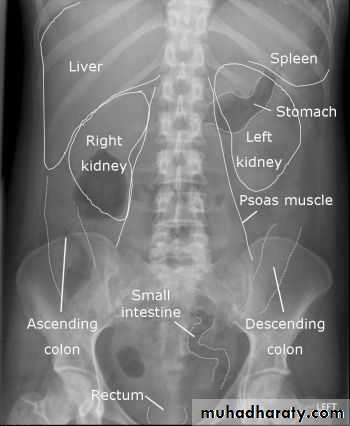

RADIOGRAPHIC ANATOMY

Intestinal gas pattern

Relatively large amounts of gas are usually present in the stomach and colon.The stomach can be readily identified by it's location, gastric rugae in the supine view and by the air fluid level beneath the left hemidiaphragm in the erect view

The duodenum often contains air and show a fluid level

Short fluid levels in the small and large bowel are normal.